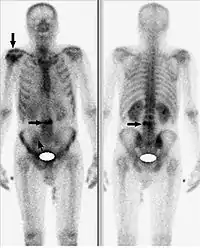

Наиболее значимым критерием проведения остеосцинтиграфии с помощью 99mTc-золедроновая кислота (Резоскан) является поиск метастатических поражений скелета. Качество проводимого исследования, главным образом, зависит от носителя и его тропности к костной ткани. Как уже отмечалось выше, в настоящее время, применяют дифосфонаты, где золедроновая кислота является максимально чувствительной к очагам повышенной резорбции кости.

Исследование начинается с внутривенного введения 99mTc-золедроновая кислота (Резоскан) с активностью 5 МБк/кг с последующим сканированием спустя 1-3 часа после инъекции, с обязательным предварительным опорожнением мочевого пузыря. Равномерное поглощение вещества костями обычно говорит о норме. Фокальное поглощение (локальное поглощение, отличающееся по интенсивности от такового в соседней кости) может свидетельствовать об аномалиях. Если фокальное поглощение интенсивнее, чем поглощение в соседней кости, это может быть признаком артрита, перелома или наличия метастазов. Менее интенсивное, чем в соседних костях, фокальное поглощение указывает на возможный некроз опухоли, лизис новообразования или последствия лучевой терапии. Размеры ни одной из коммерчески доступных гамма-камер не позволяют получить изображение всего тела взрослого человека без перемещения камеры или пациента. Таким образом, сканирование скелета проводится с помощью перемещения камеры вдоль длинной оси пациента или перемещения пациента вдоль камеры. Для сканирования скелета детекторы размещают в положениях 90° и 270°, пациент лежит на спине ногами по направлению к гентри. Затем стол вместе с пациентом перемещается в точку начала сканирования, в которой голова пациента находится находится в поле зрения камеры. Во время исследования пациент и стол перемещаются таким образом, что сканирование идёт с головы до ног. Следует отметить, что получение изображений всего тела («whole body»), которые представляют собой относительные значения поглощения радиомаркера в области головы, груди, брюшной полости и ног, требует точного кодирования и сопоставления параметров сканирования и движения пациента. Большинство таких процедур проводится с помощью систем, содержащих две гамма-камеры, так что передняя и задняя проекции создаются одновременно.

Остеосцинтиграфия